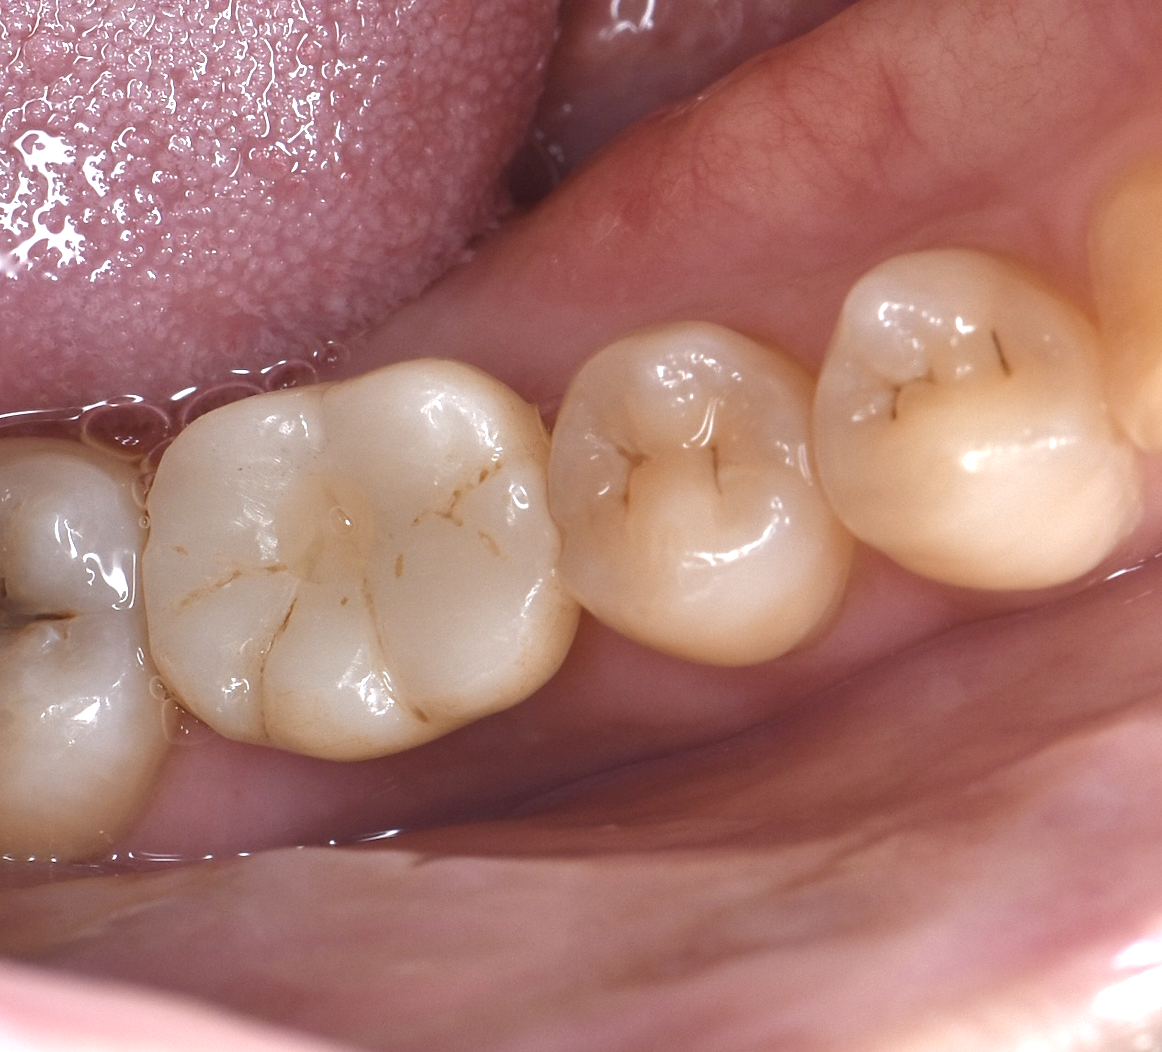

Before

40代女性 虫歯で再治療不可の部分をインプラントに

治療期間 4ヶ月 費用65万円

デメリット:費用が高い、外科処置が必要

After

骨が薄い部分に対してインプラント埋入と同時に

骨を足す処置(GBR)を行いました

*画像左上